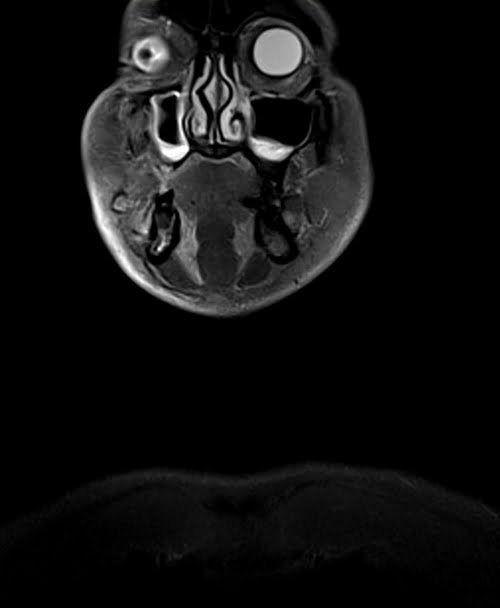

Neck MRI coronal STIR images